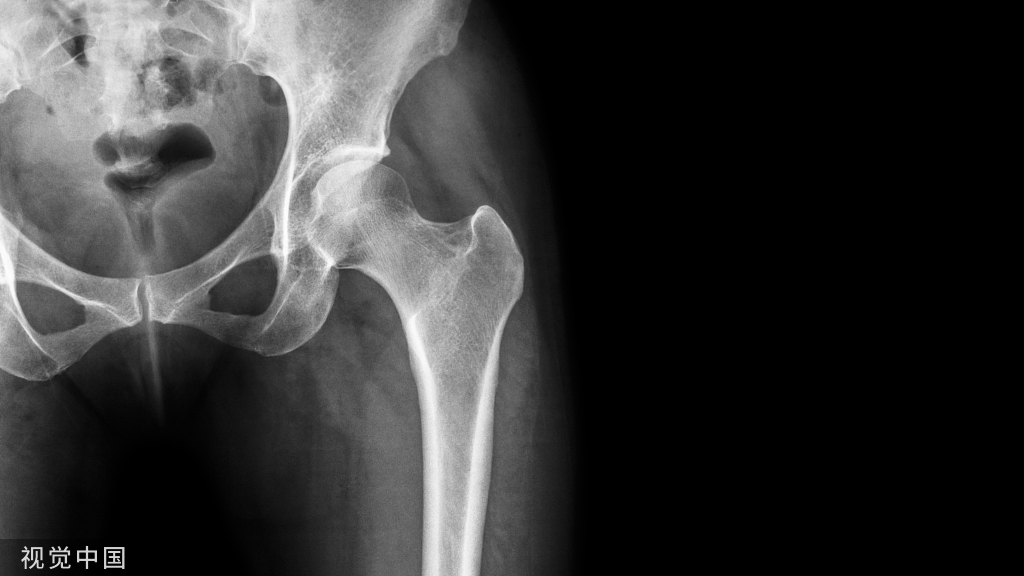

股骨转子间、转子下骨折骨折是一种多发于老年人的骨折,虽然常见,但并不简单。医生的手术技巧对治疗预后非常重要!

完善的术前影像学检查和熟练的阅片技巧

单纯的骨盆平片是不够的,需拍患肢全长片以排除远端的骨折

行右股骨转子间骨折CT平扫加重建,以明确骨折方向便于术前定手术方案和术中精确复位。